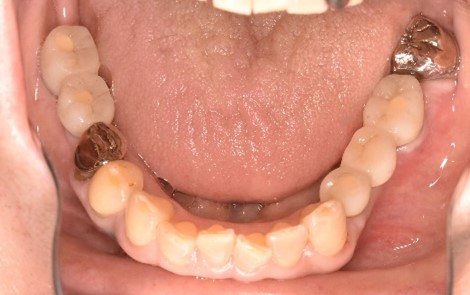

女性Mさん 40代(インプラント)

下、左右歯がないところに歯を入れたい。

右下に2本、左下に1本インプラントを入れました。

所感

下顎左右奥の歯がないところに、インプラント治療を希望されて来院されました。X-Guideを使用し埋入しました。治療後「左右の奥歯でしっかり噛めてうれしいです。」と、とても喜んでくださいました。

インプラント3本:¥363,000×3本=¥1,089,000(税込)

Before

After